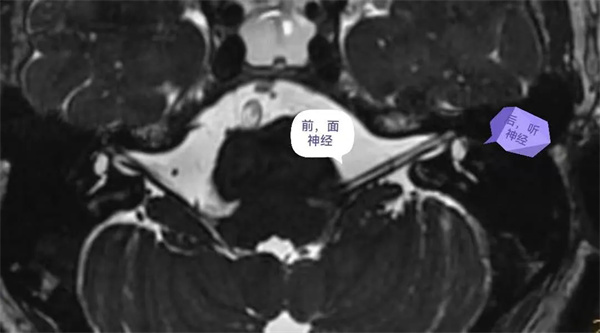

圖3:軸位圖像能清晰顯示、分辨顱內(nèi)腦池段、內(nèi)耳道段面神經(jīng)(前)和聽神經(jīng)(后)。